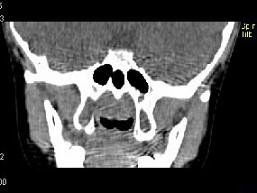

女,8岁,头痛,鼻塞半年余,CT如图所示,最可能诊断为 ( )A、神经纤维瘤B、咽后脓肿C、鼻咽部炎症D、腺样体肥大E、鼻咽癌

问题 女,8岁,头痛,鼻塞半年余,CT如图所示,最可能诊断为 ( )

选项 A、神经纤维瘤 B、咽后脓肿 C、鼻咽部炎症 D、腺样体肥大 E、鼻咽癌

答案 D